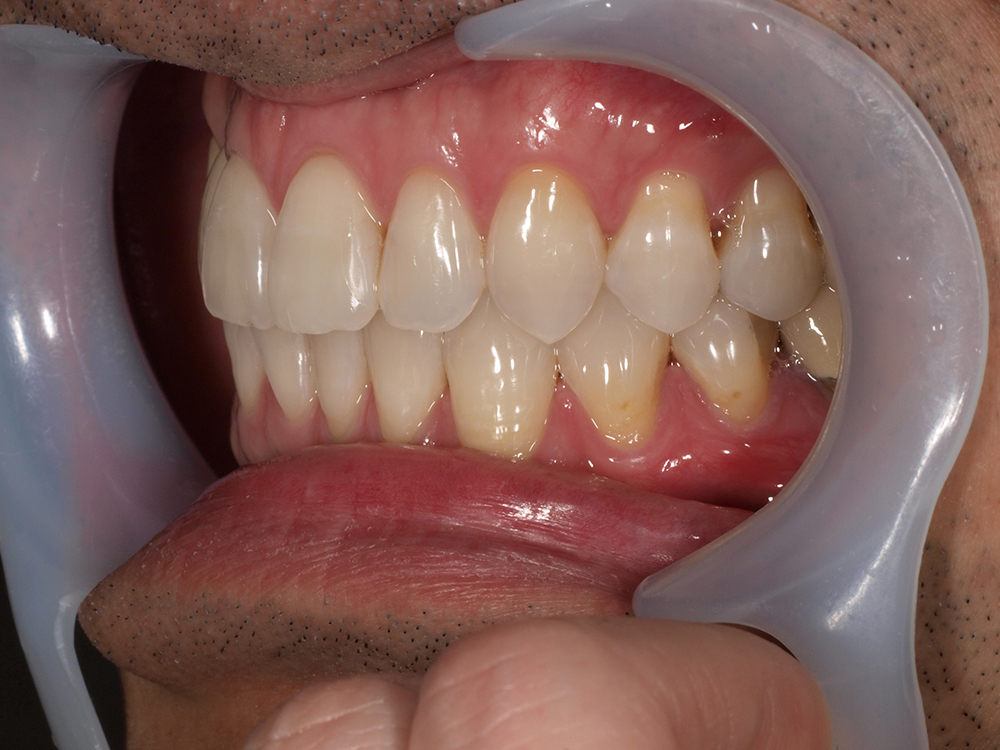

45歳 男性 医療関係者紹介

- 主訴

- 右前歯が取れた(右上2)

- 処置内容

-

1本インプラント埋入+再生療法

抜歯即時埋入⇒抜歯を行い、同時にインプラント埋入(即時埋入)

- 治療費用

- 上顎:約40万円(税込)

- 治療期間

- 約11か月

- リスク

- 上部構造物、仮歯の破折、術後の腫れ(3日)、人工歯根脱落リスクがあります